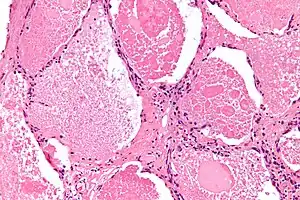

Micrograph of pulmonary alveolar proteinosis, showing the characteristic airspace filling with focally dense globs referred to as chatter or dense bodies. H&E stain.

Lung washings or tissue for histopathologic analysis are most commonly obtained using bronchoalveolar lavage and/or lung biopsy.[12] Characteristic biopsy findings show filling of the alveoli (and sometimes terminal bronchioles) with an amorphous eosinophilic material, which stains strongly positive on PAS stain and the PAS diastase stain. The surrounding alveoli and pulmonary interstitium remain relatively normal.[13] Electron microscopy of the sample, although not typically performed due to impracticality, shows lamellated bodies representing surfactant.[14] An alternative diagnosis with similar histomorphologic findings is Pneumocystis jirovicii pneumonia.[14]

Lung washings characteristically yield a fluid which is "milky"composition. Under the microscope, samples show 20-50 micrometer PAS-positive globules on a background of finely granular or amorphous PAS-positive material. There is typically a low numbers of macrophages and inflammatory cells (although this is variable).[13][14]